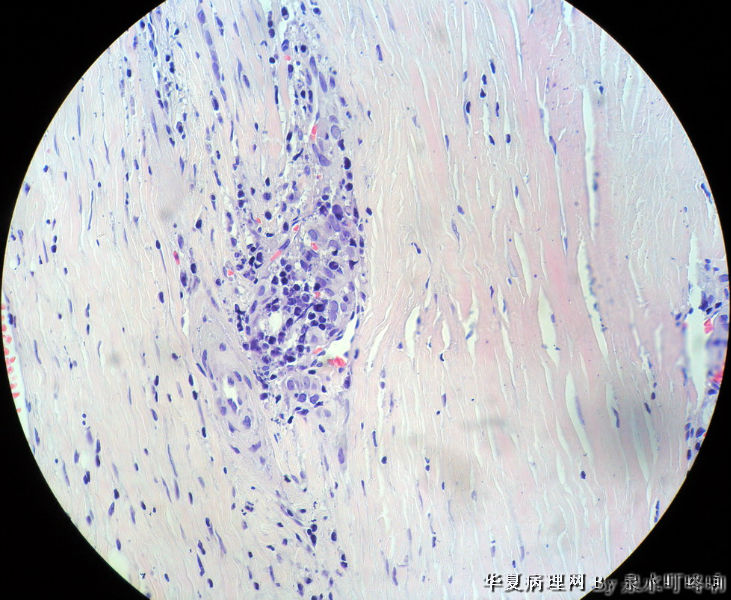

120212,女,55岁,左颈部肿物七年余。

大体:灰白肿物一个,大小约2.1×1.5×1.3厘米。表面光滑,包膜完整,切面灰白,部分包膜有钙化。

与手术医生沟通,肿物位于左颈部靠近甲状腺部位,比较浅(门诊手术),手术医生认为是淋巴结部位。

• 左颈部肿物图3

图3

厚包膜、蕈状浸润----滤泡癌。